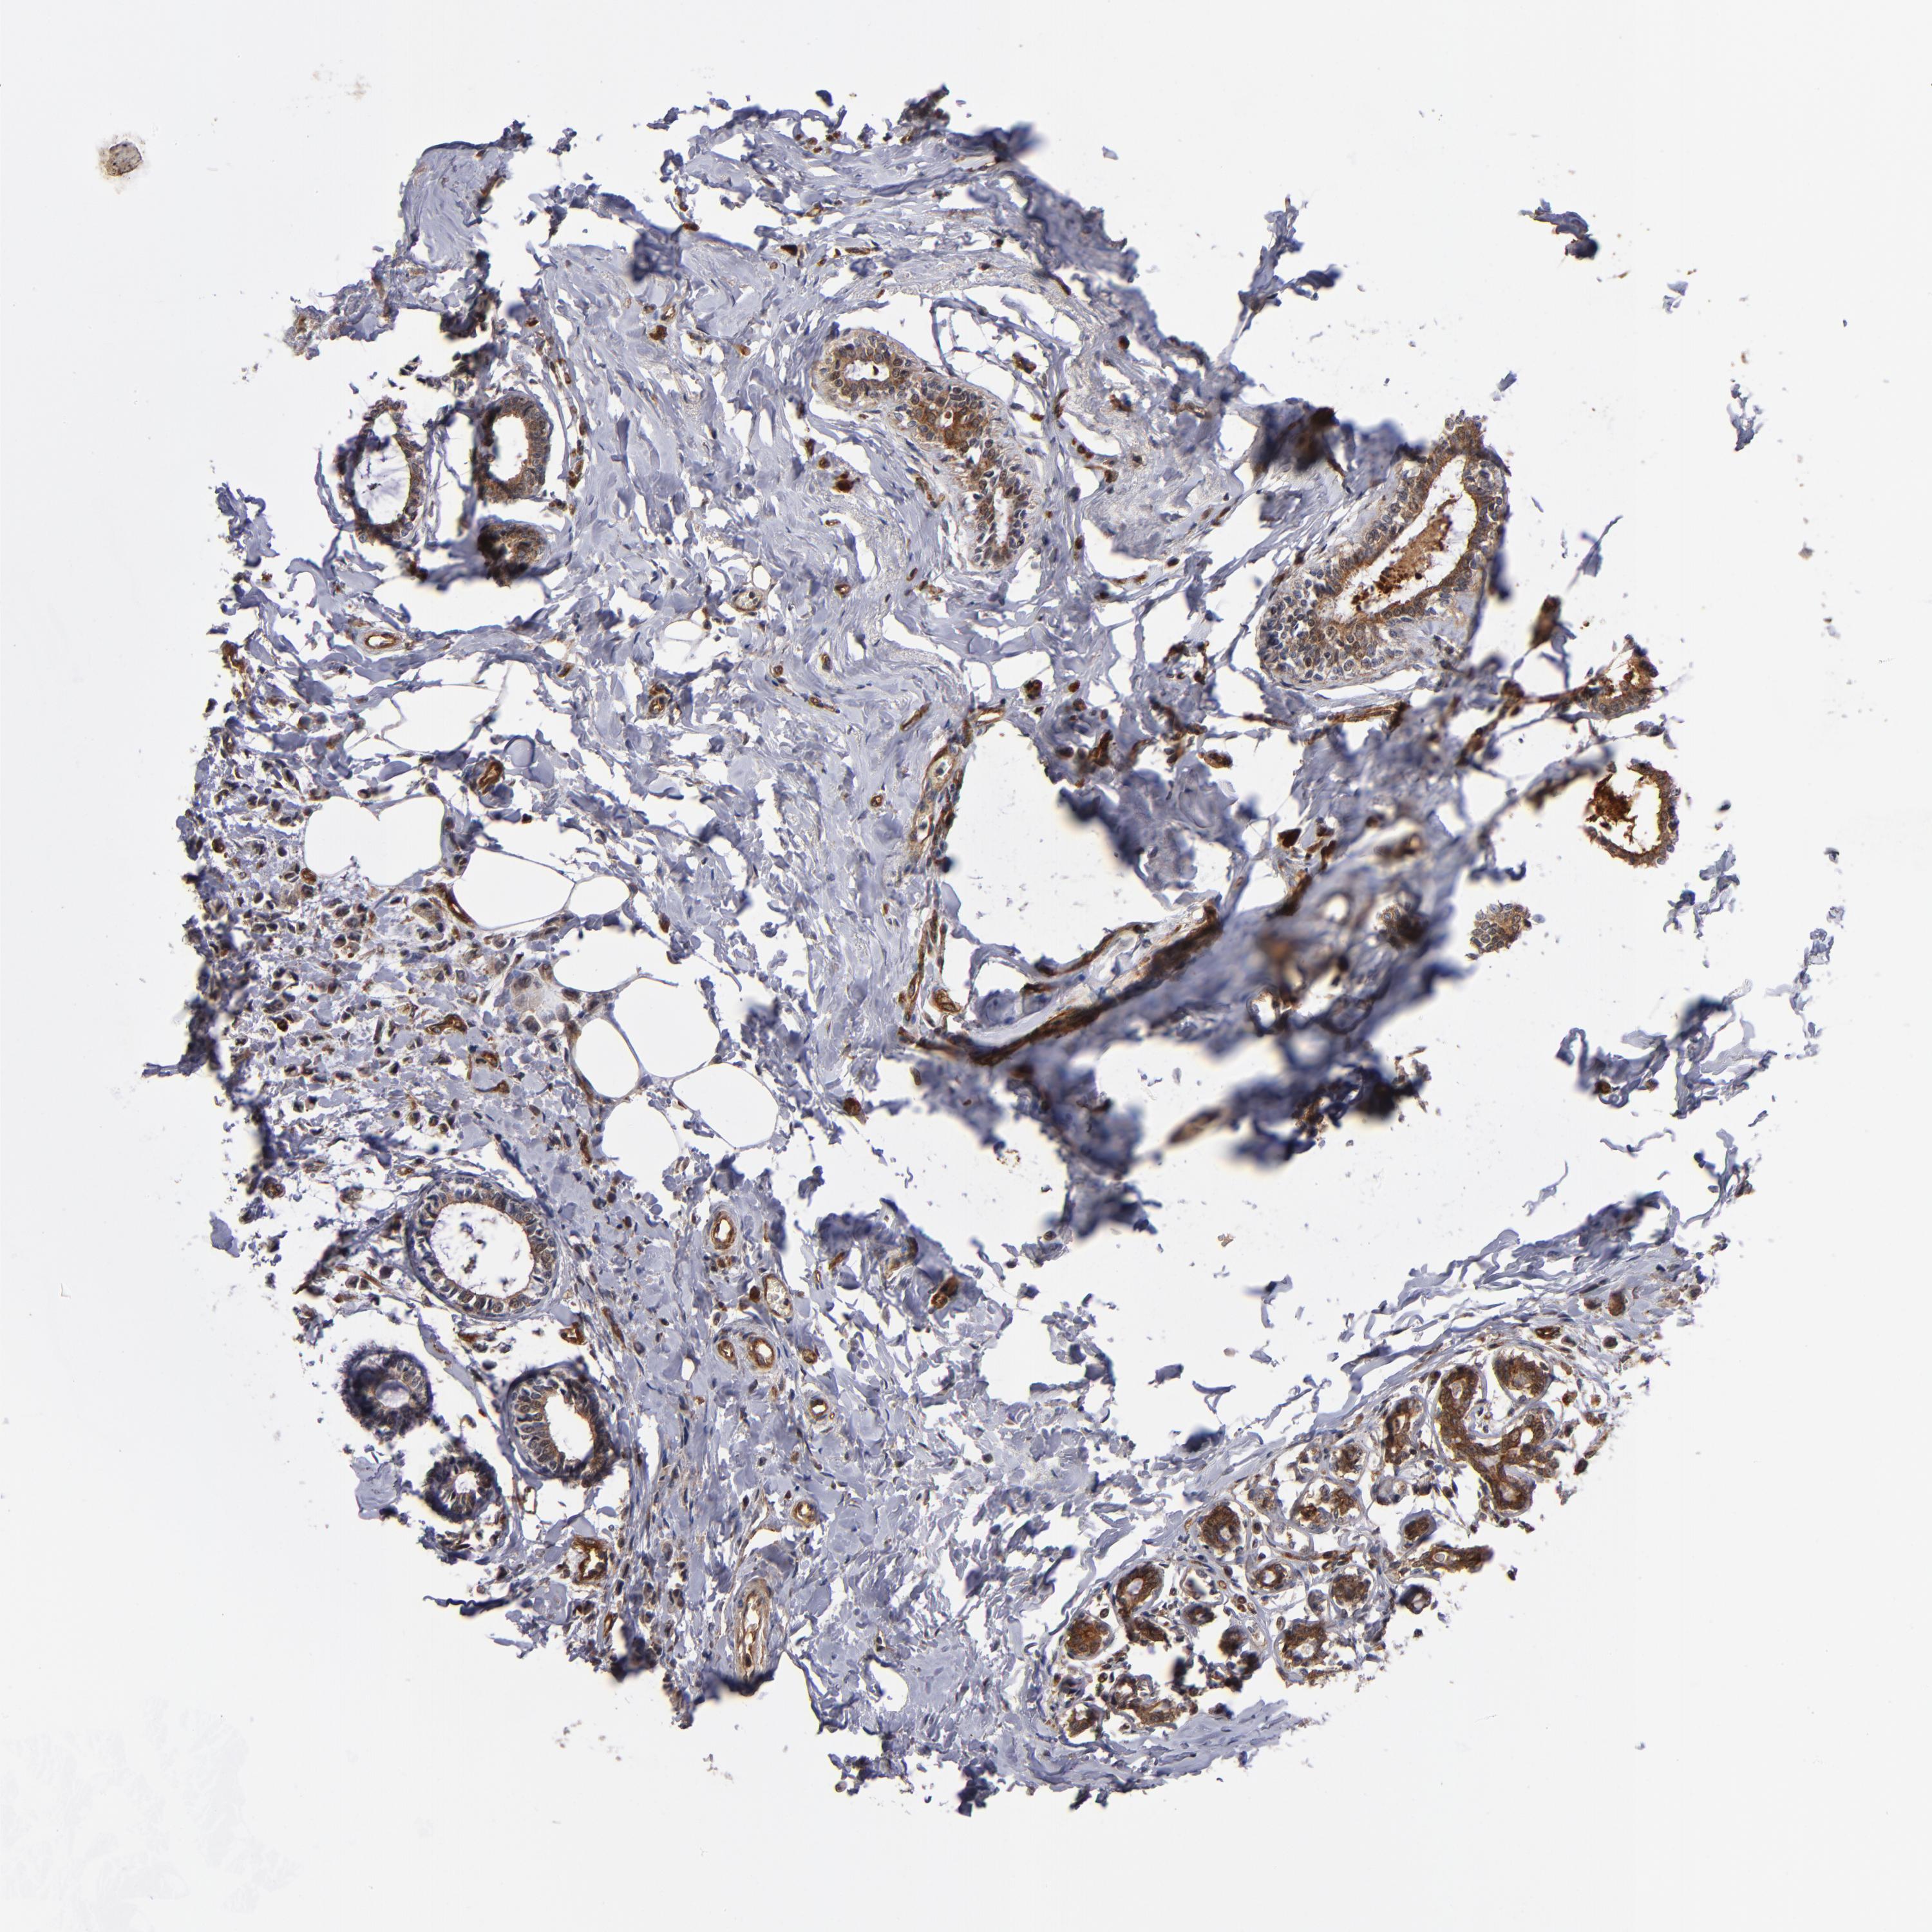

CANCER BREAST CANCER Show tissue menu

BRCA TCGA BRCA VALIDATION PROTEIN EXPRESSION

ANTIBODIES

AND

VALIDATION